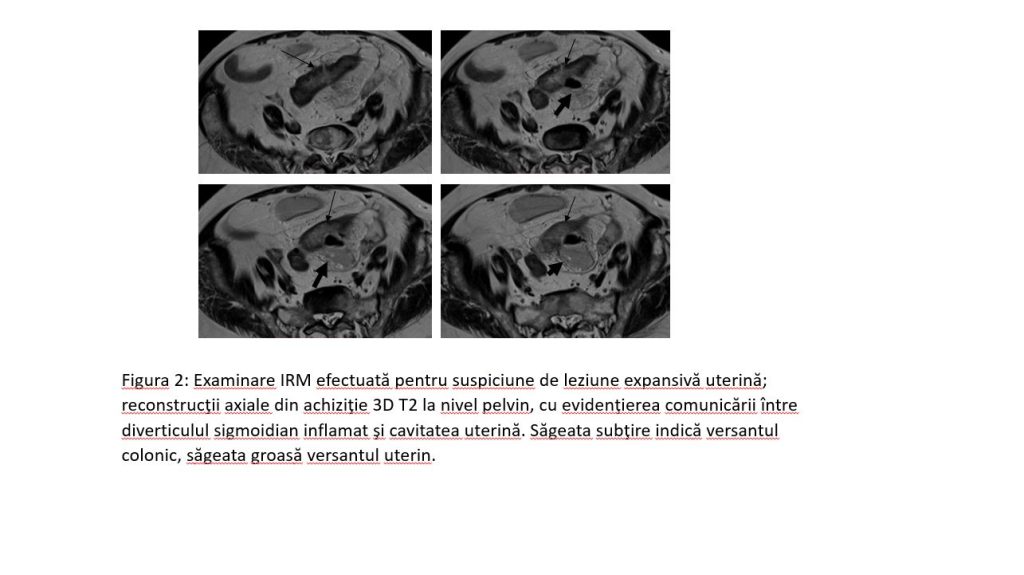

Figura 2: Examinare IRM efectuată pentru suspiciune de leziune expansivă uterină; reconstrucţii axiale din achiziţie 3D T2 la nivel pelvin, cu evidenţierea comunicării între diverticulul sigmoidian inflamat şi cavitatea uterină. Săgeata subţire indică versantul colonic, săgeata groasă versantul uterin.

Discuție caz 3: diverticulita acută reprezintă inflamația unui diverticul intestinal iar imagistic se pune în evidență îngroșare parietală a colonului în vecinatatea diverticulului, infiltrație difuză în benzi a grăsimii din vecinătate şi, mai rar, formare de abces sau traiect fistulos.

Acești pacienți ajung de obicei la examinare CT, în cazul nostru am efectuat examinare IRM deoarece pacienta s-a prezentat la consult ginecologic pentru dureri pelvine şi secreții în cantitate mare şi la ecografie s-a ridicat suspiciunea de formațiune tumorală uterină.